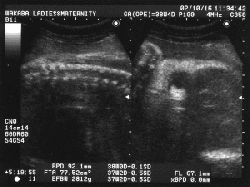

2002年10月16日  38週3日 妊娠10ヶ月

←  …先生、失敗ですか?ヾ(ーー;

わけわからん写真。